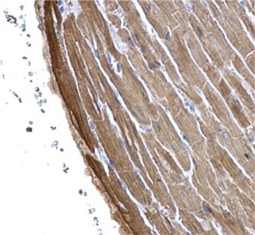

Cardiomyocytes make up the striated heart muscle. Unlike skeletal muscle cells, cardiomyocytes have a branching morphology.

Cardiac Troponin T antibody [1C11] GTX28295

Cardiac Troponin T antibody (GTX28295)